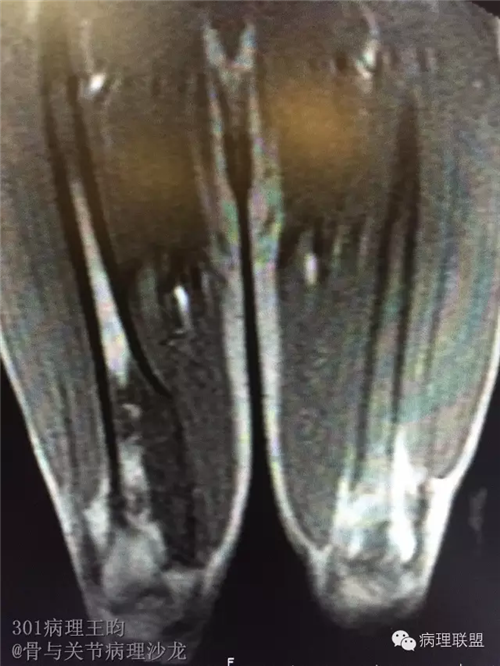

右股骨髓内高分化低级别骨肉瘤or骨纤维异常增殖症(Fibrous Dysplasia)?

男,36岁,活动后疼痛,发现右股骨远端肿瘤。